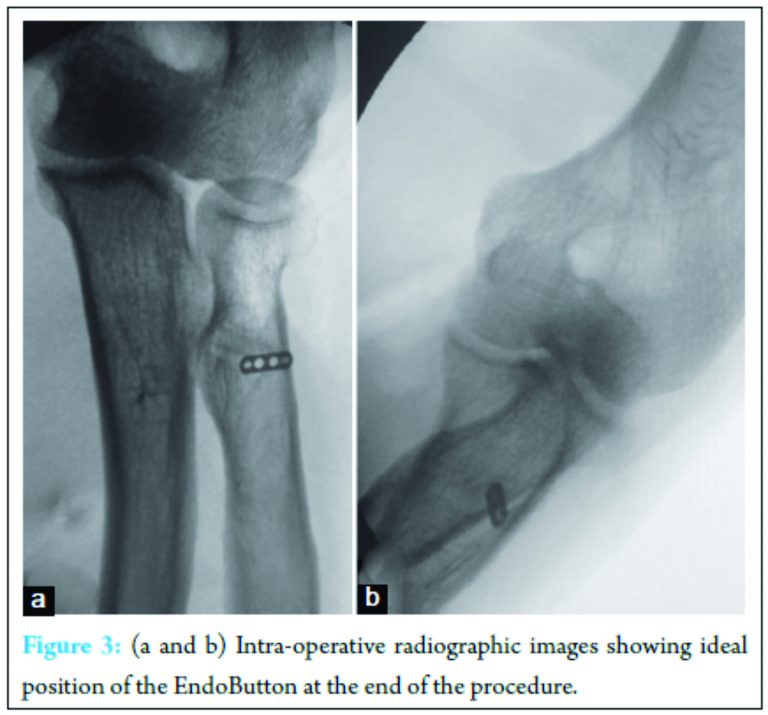

Care is taken to ensure that the tendon is appropriately aligned. Placing the elbow in 20-30° flexion and full supination, hold the looped EndoButton at the tip of long thin straight artery forceps or EndoButton holder and pass through both drill holes to deliver the EndoButton to the dorsal aspect of the proximal radius (Fig. 1f). Once the button cleared the posterior cortex, the deployment instrument was removed while the button deployed itself, locking into place on the posterior cortex. Pulling on the sutures shuttles the biceps tendon into the radius. The sutures were tensioned until the tendon was in contact with the posterior cortex. By placing tension onto the trailing suture, the EndoButton locks into position and prevents proximal migration of the tendon (Fig. 1g). Fluoroscopy is useful to assess the position of the EndoButton as it is advanced through the radius and locked into position (Fig. 1h, 3a and b). Using both suture threads, knots are tied under tension after back passing one of the suture threads through the biceps tendon just adjacent to anterior cortex (Fig. 1h).

We recommend using C-arm image/fluoroscopy, while passing the guide wire, drilling the cortex and confirming the position of EndoButton before tightening the sutures. This avoids mal trajectory of the guide wire, blowing out the posterior cortex with first drill, intramedullary dislodgement of the EndoButton just before tightening the suture threads and inter-positioning of the PIN or soft tissue between the posterior cortex and the EndoButton, which is depicted by a gap between the EndoButton and the posterior cortex in a lateral view image.